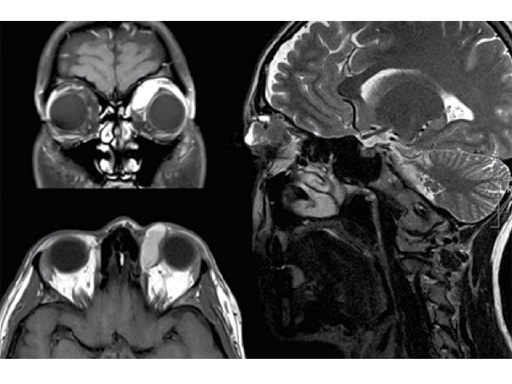

Resection of orbital lymphangioma in a 29-year-old woman.

Case provided by Christian Matula, Wien, Austria

Fig 1 Preoperative images.